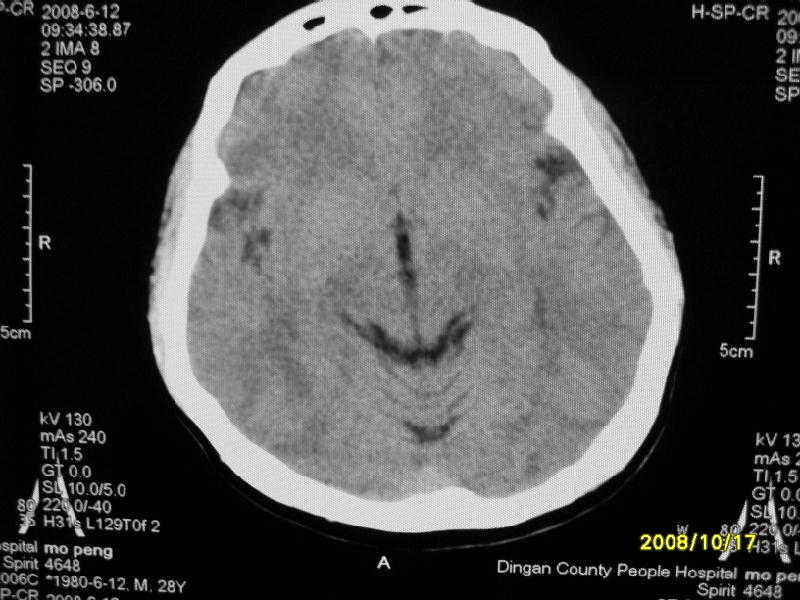

检查名称:     ct颅脑平扫           男     28岁

表现:左顶叶见斑点状致密影。边缘清,大小约0。3*1。0cm,余脑实质密度及灰白质结构示见异常。脑室系统大小,形态,密度未见异常。脑沟。脑裂。脑池未见异常密度影。中线结构无移位。

印象:左顶叶少许钙化灶

左顶叶见斑点状致密影。边缘清,大小约0。3*1。0cm,余脑实质密度及灰白质结构示见异常。脑室系统大小,形态,密度未见异常。脑沟。脑裂。脑池未见异常密度影。中线结构无移位。

印象:左顶叶少许钙化灶。

左顶叶见斑点状致密影